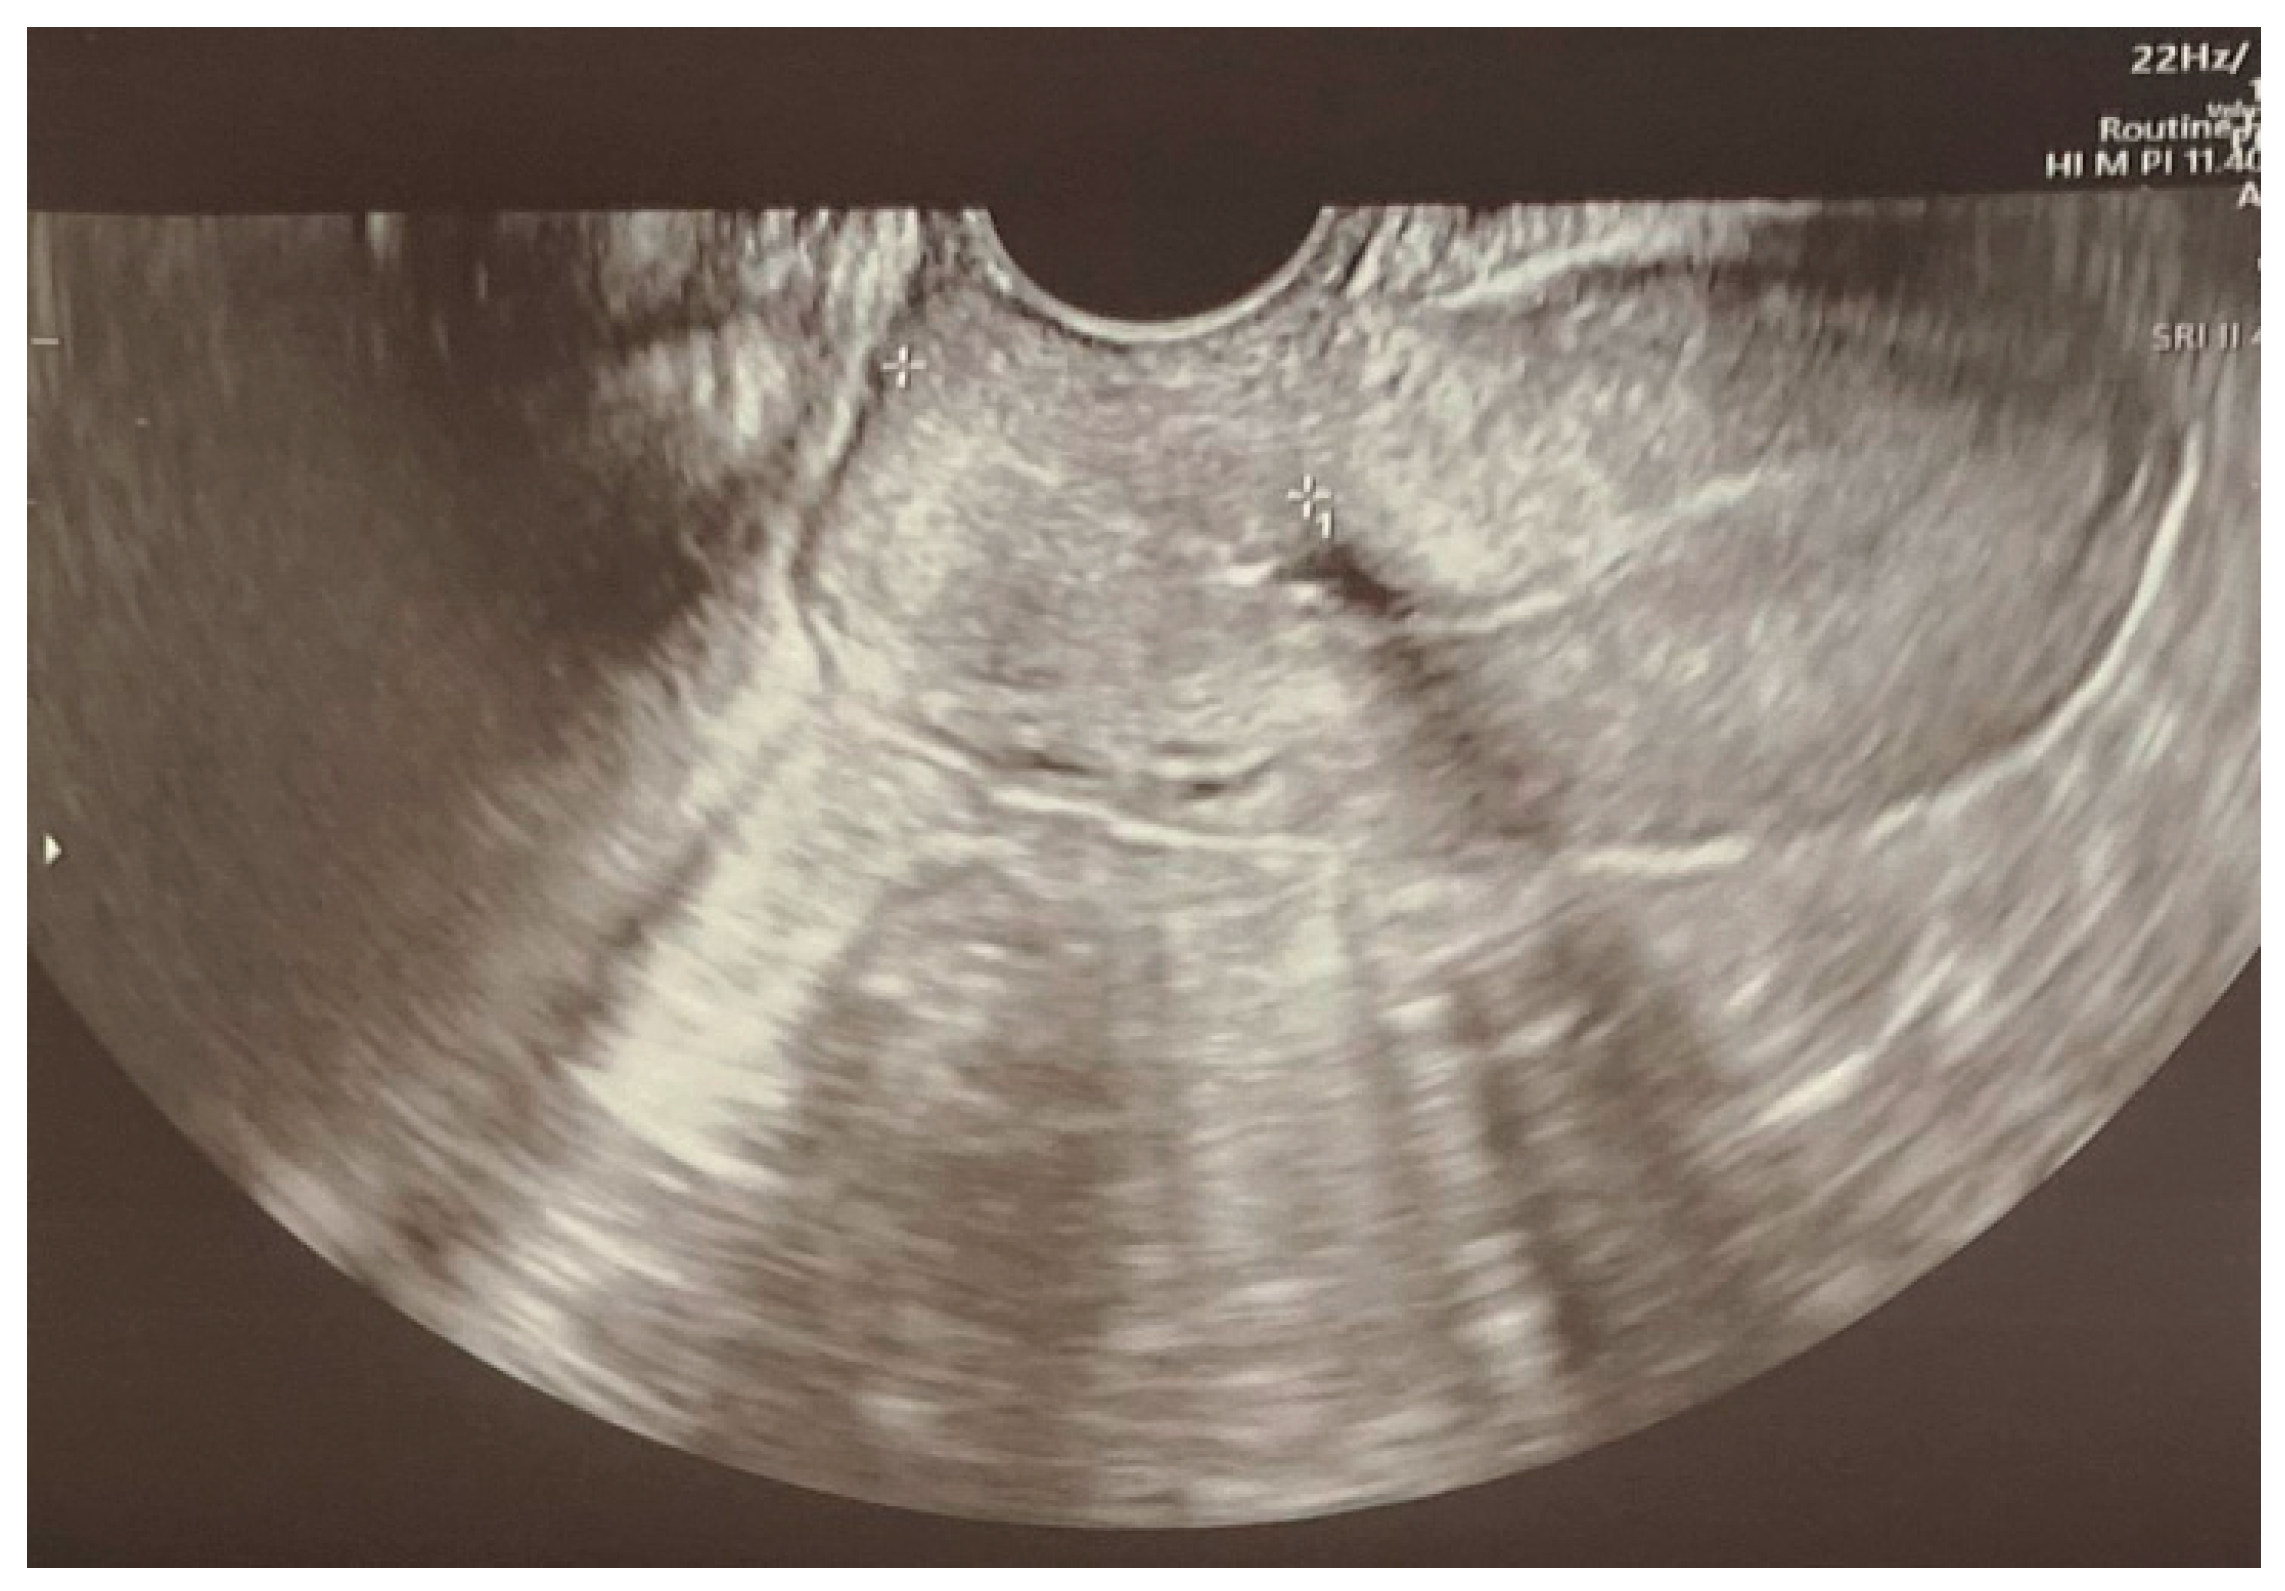

MR of the brain reveled “symmetrical, bilateral vasogenic edema of the subcortical white matter, in both cerebral hemispheres and all lobes—severe changes, causing partial tightening of the cerebral sulci with signs of subarachnoid hemorrhage (SAH) on the vault at the right parietal and left frontal lobes. The ventricular system is positioned medially, symmetrical, not dilated. No signs of compression in the posterior cranial fossa were demonstrated. Conclusion: the morphology of severe changes in the cerebral white matter primarily supports the diagnosis of posterior reversible encephalopathy syndrome (PRES), probably secondary to preeclampsia/eclampsia” (Figure 1).

Figure 1. Brain MR performed at the tertiary emergency department with signs of SAH on the vault at the right parietal and left frontal lobes.